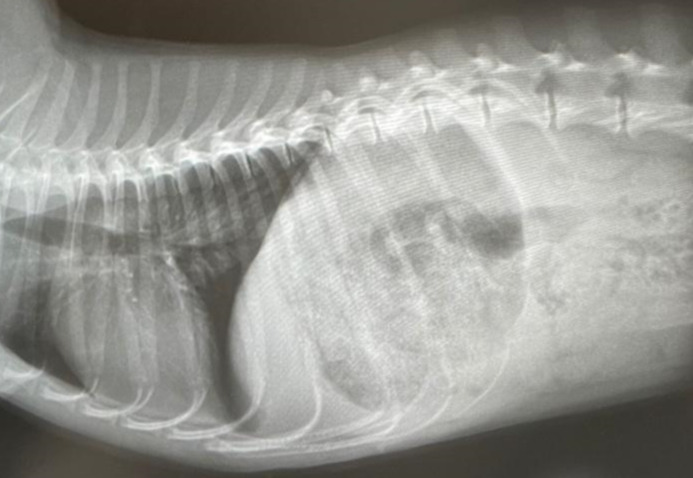

KakaoTalk_20211022_154448904.jpg 내원 당시 배출되지 못한 분변으로 가득 차 있던 하쿠의 작은 뱃속 상황

끝내 어떤 하루엔 궁금증을 참지 못하고, A의 도움을 받아 동물병원이 마친 후에야 아무도 없는 틈을 타(그때는 입원환자도, 응급진료도 없던 때라서) 처치실에 잠행했다(이것 조차도 A가 병원 실험실의 학부생이어서 가능했다). 이 시바견의 이름은 하쿠, 사진 속 딱 그 모습처럼 작고 가냘팠다. 영양 대사가 잘 이루어지지 않아서인지 앙증맞고 통통한 보통의 강아지와 같은 모습이 아니라, 그저 작고 야윈 새끼 여우 같았다. 평범하지 않은 모습으로 인한 신기함과 아기 강아지라는 귀여움에 빠진 것도 잠시, 이 친구가 선천성 항문 폐쇄증(anal atresia)으로 입원하여 수술을 기다리고 있다는 사실을 듣게 되었다.

선천성 항문폐쇄증이란 태어나면서부터 항문 없이 태어나는 기형이다. 따라서 정상적인 소화의 결과인 배변활동 또한 불가능한데, 항문을 재건하는 수술을 하지 않으면 배출되지 못하는 체내 독소가 쌓여 독혈증 및 합병증으로 죽게 된다. 한 번 봤을 뿐인데도, 마치 그 아이를 만난 것은 내 일생일대의 운명인 것처럼, 또는 이 일이 내 일인 것처럼 마음이 아파왔다. 하지만 그때까지만 해도 14년 반 동안 함께했던 내 가족, 내 동생, 방울이(강아지)가 죽은 지 얼마 되지 않았고, 충격과 슬픔이 너무 커서 다시는 개를 키우지 않으리라 다짐했었다. 때문에, 부디 이 안타까운 작은 강아지가 잘 수술받아 새로운 삶을 살 수 있기를 바랐지만, 훗날 나 자신이 이 똥강아지를 책임지게 될 것이라는 예상은 하지 못했다.